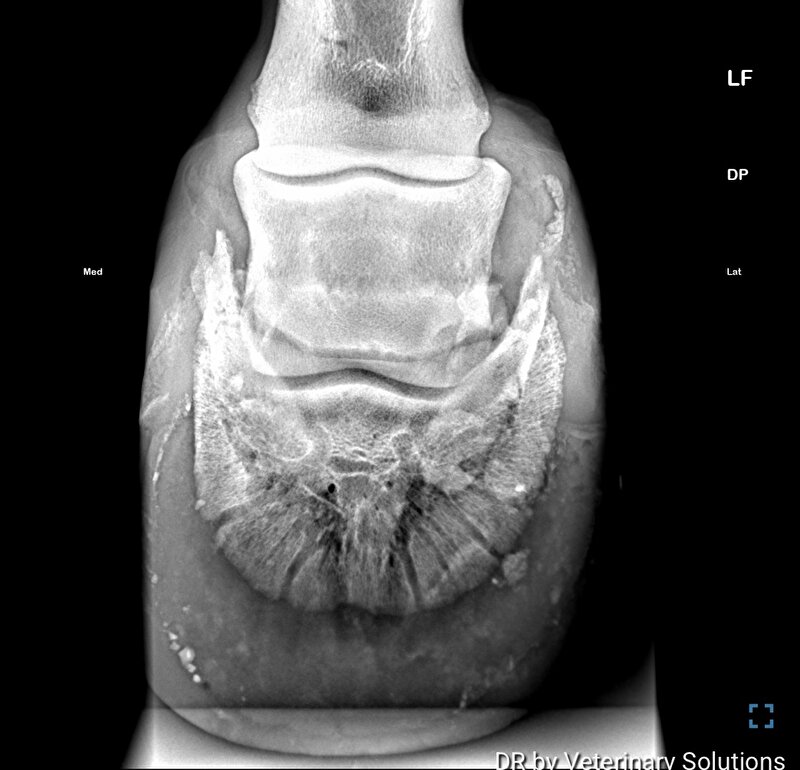

zefiros schreef:Hier best erge verbening vh hoefkraakbeen beide hoeven.